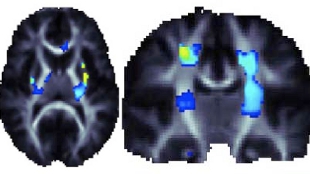

脑部扫描发现基因变体改善了大脑的完整性(图中黄蓝区域)

研究人员更进一步研究了两个铁代谢基因,发现其中一个基因HFE的多态性——HFE调控细胞吸收携带铁的转铁蛋白——与高铁水平和白质完整性改善有关。